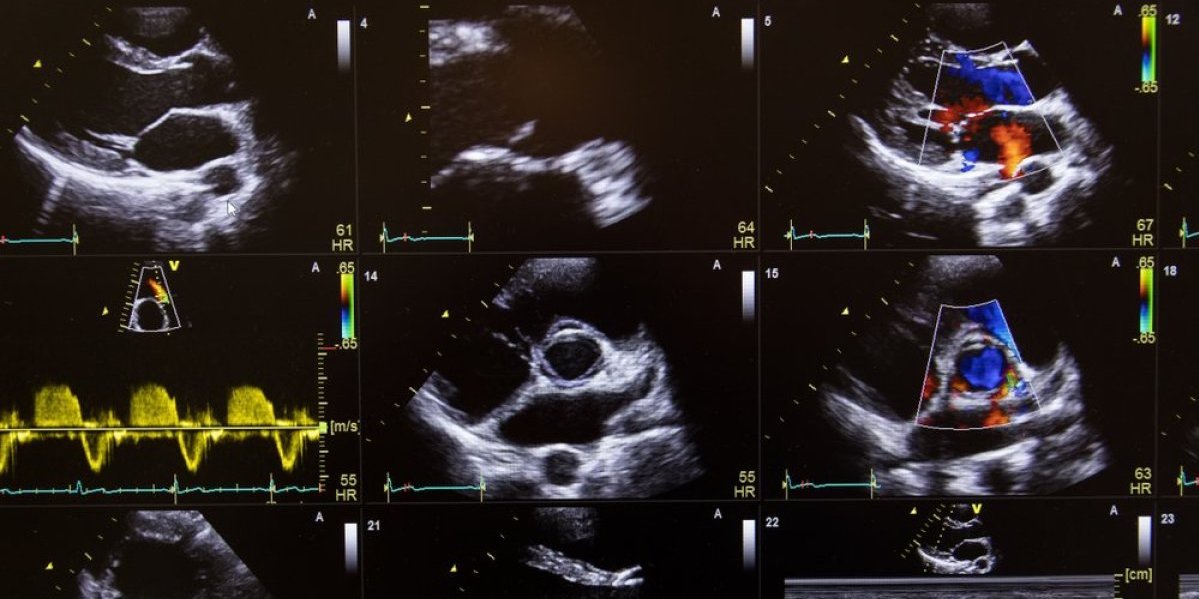

Tim istraživača prvi put je zabeležio izuzetno rano formiranje srca pomoću usporenih snimaka razvoja miševa u embrionalnoj fazi. Ova revolucionarna tehnika omogućila je da se u stvarnom vremenu posmatra kako se ćelije srčanog mišića spontano organizuju u oblik nalik srcu, još u najranijem stadijumu razvoja.

Glavni autor studije, dr Kenzo Ivanovič sa Instituta za zdravlje deteta Great Ormond Street u Londonu, rekao je da je ovo prvi put da srčane ćelije kod sisara mogu da se prate tako detaljno tokom razvoja. On objašnjava da su morali da razviju metod uzgoja embriona u laboratorijskim uslovima tokom više dana, što je dovelo do potpuno neočekivanih otkrića.

Koristeći naprednu svetlosnu mikroskopiju i fluorescentne markere koji boje ćelije srca u različite nijanse, tim je snimao kako se te ćelije kreću i formiraju primitivni oblik srca. Snimci su rađeni svaka dva minuta tokom 40 sati, prateći kako se ćelije organizuju, dele i zauzimaju tačno određene pozicije.

U vrlo ranoj fazi razvoja, poznatoj kao gastrulacija, istraživači su primetili da ćelije koje će kasnije postati srce ne deluju nasumično, već se kreću jasno određenim putevima jedne prema komorama (ventrikulama), druge prema pretkomorama (atrijumima). Time su pokazali da proces formiranja srca započinje mnogo ranije nego što se ranije mislilo, piše "Guardian".

Ivanovič navodi da ova otkrića mogu fundamentalno promeniti razumevanje kako se srce razvija, jer se pokazuje da ono što izgleda kao haotično kretanje ćelija ustvari prati precizne obrasce.

Istraživači se nadaju da će ovo otkriće unaprediti lečenje urođenih srčanih mani kod ljudi.